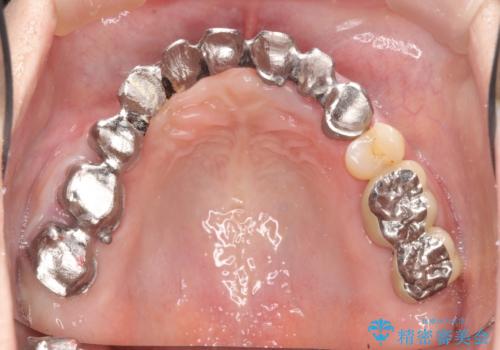

- 90万円 (仮歯×9 メタルボンドクラウン×9)費用は治療当時の料金となります

ブリッジは欠損した部位に臨在する歯を削り、被せなければいけないというデメリットがありますが反面噛む力が強い場合連結することで強大な咬合力に対抗できるというメリットも存在します。